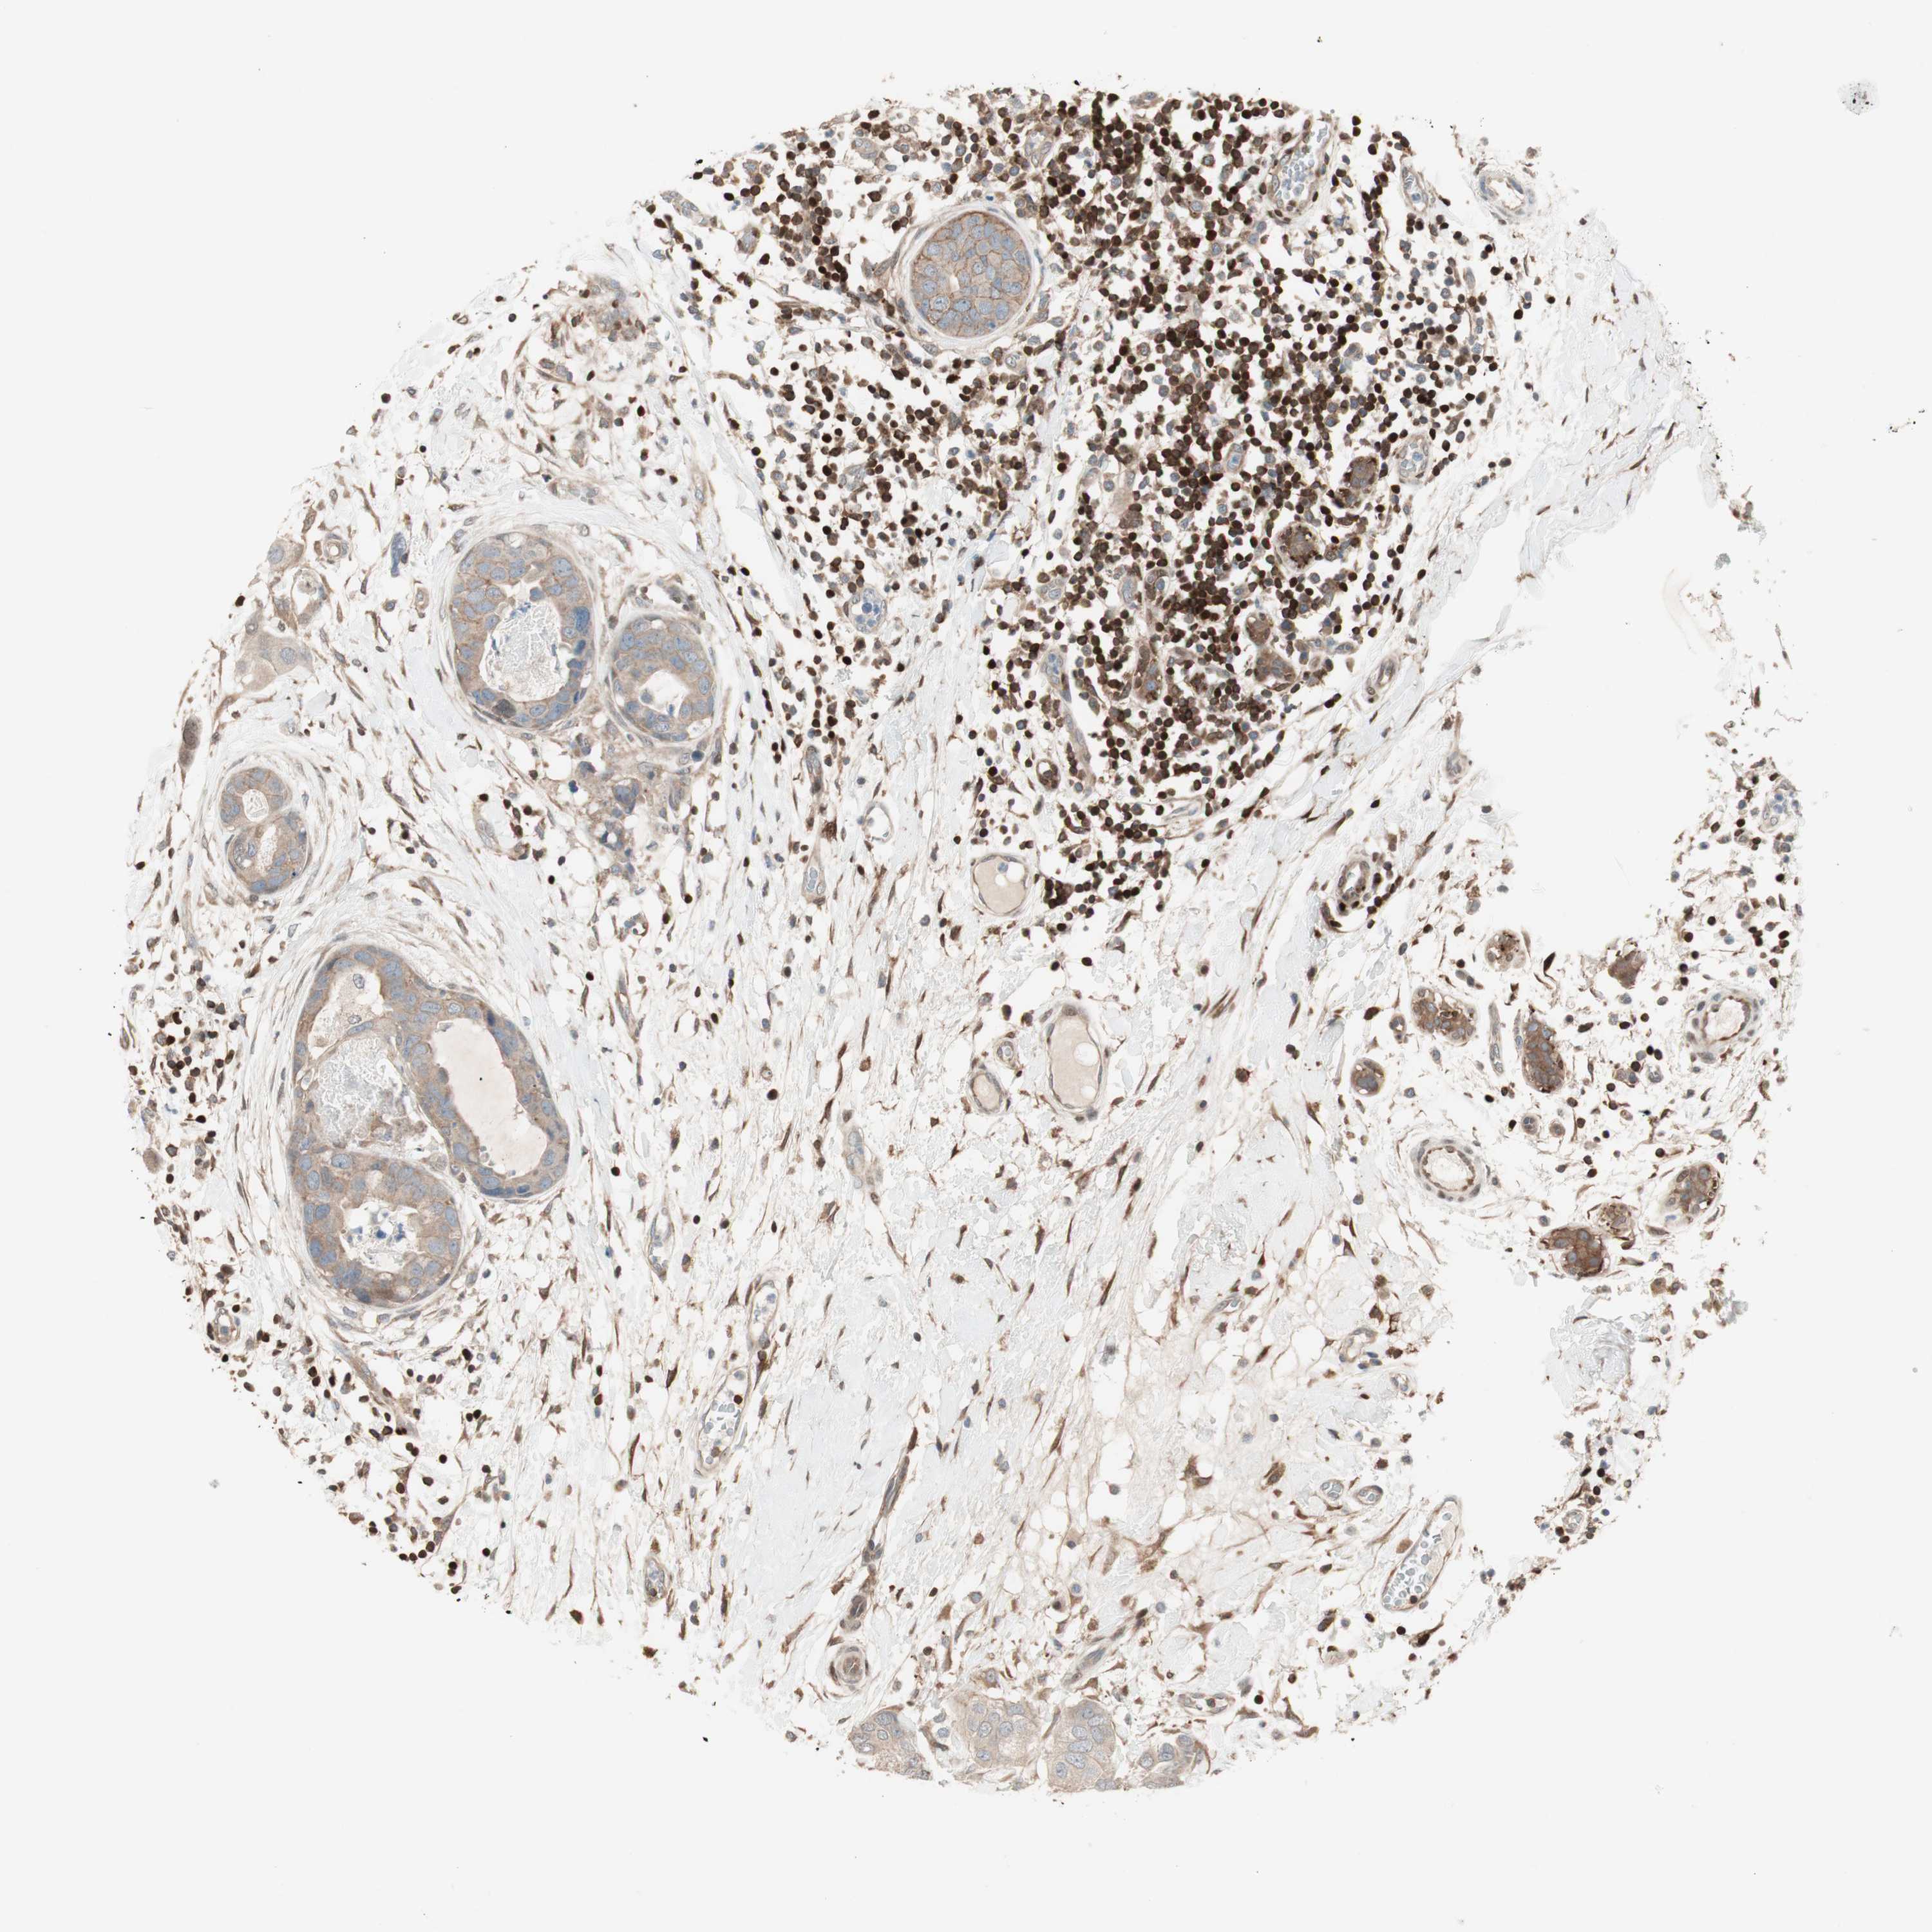

CANCER BREAST CANCER Show tissue menu

BRCA TCGA BRCA VALIDATION PROTEIN EXPRESSION